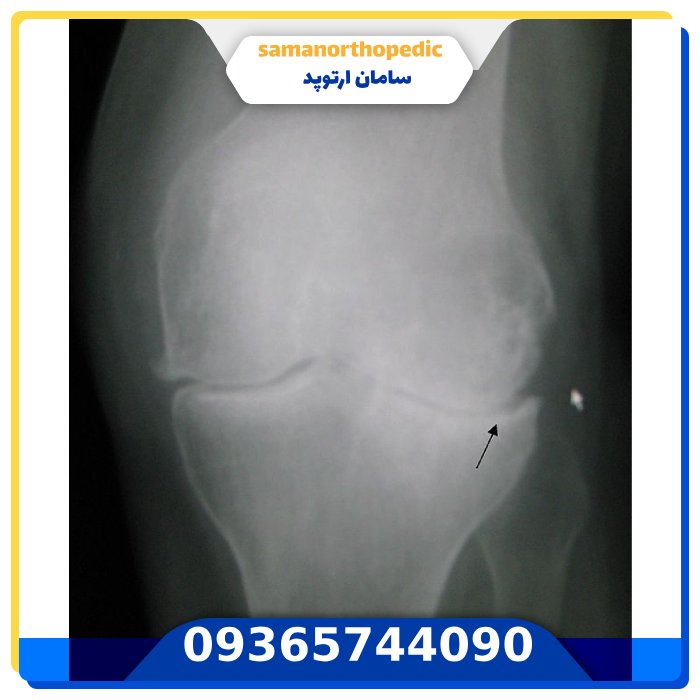

تست انحراف زانو

در برخی موارد، پزشک ممکن است برای تأیید تشخیص انحراف زانو و بررسی میزان انحراف، از تست های تصویربرداری مانند اشعه ایکس یا MRI استفاده کند.